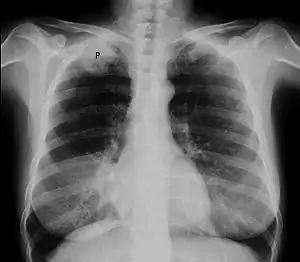

Chest X-ray showing a Pancoast tumor (labeled as P, non-small cell lung carcinoma, right lung), from a 47-year-old female smoker.

Diagnosis of Pancoast tumor is usually made after evaluating clinical symptoms and imaging. Chest X-ray is a good screening test even though a CT scan of the chest can provide a better resolution and extent to which internal organs are being compressed.